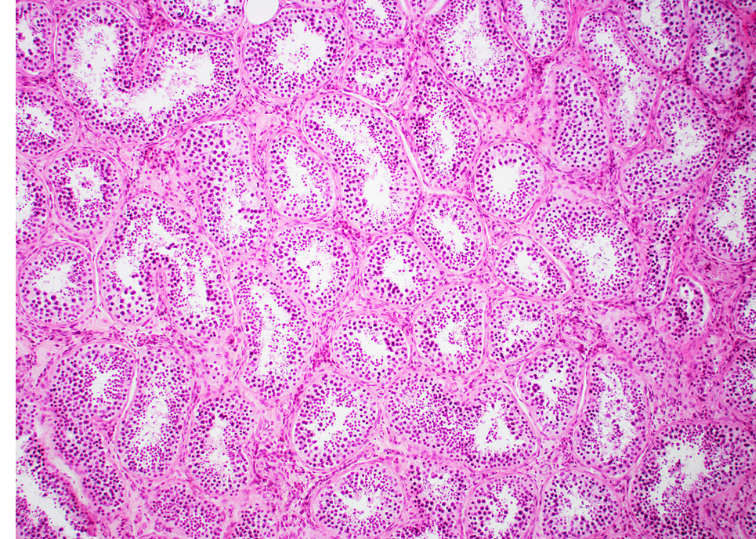

testis (cross section)

tunica albuginea

seminiferous tubules

spermatogonia

primary spermatocytes

spermatids

interstitial cells